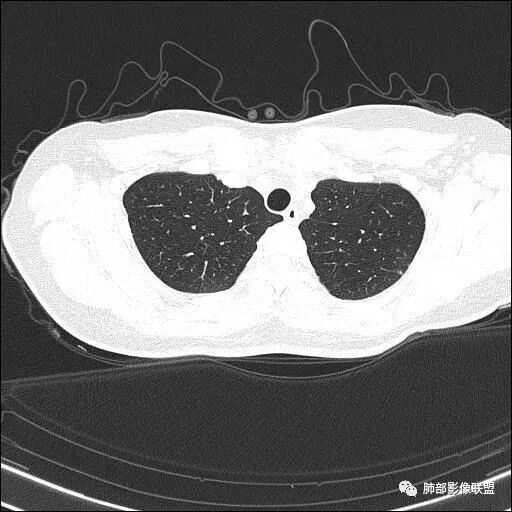

【每日晨读】双肺上叶多发薄壁空洞

两肺多发病灶

分布特点:上肺胸膜下

2.双肺多发薄壁空洞影、条索影及结节影,边界较清楚,密度偏高不柔和,散乱,但有成簇倾向或堆积感,胸膜下分布为主,双肺上叶分布为主。

3.空洞相当不规则,缺乏张力,未见血管穿行,未见壁结节,未见液平。

4.双肺门及纵隔未见肿大淋巴结。未见胸腔积液。